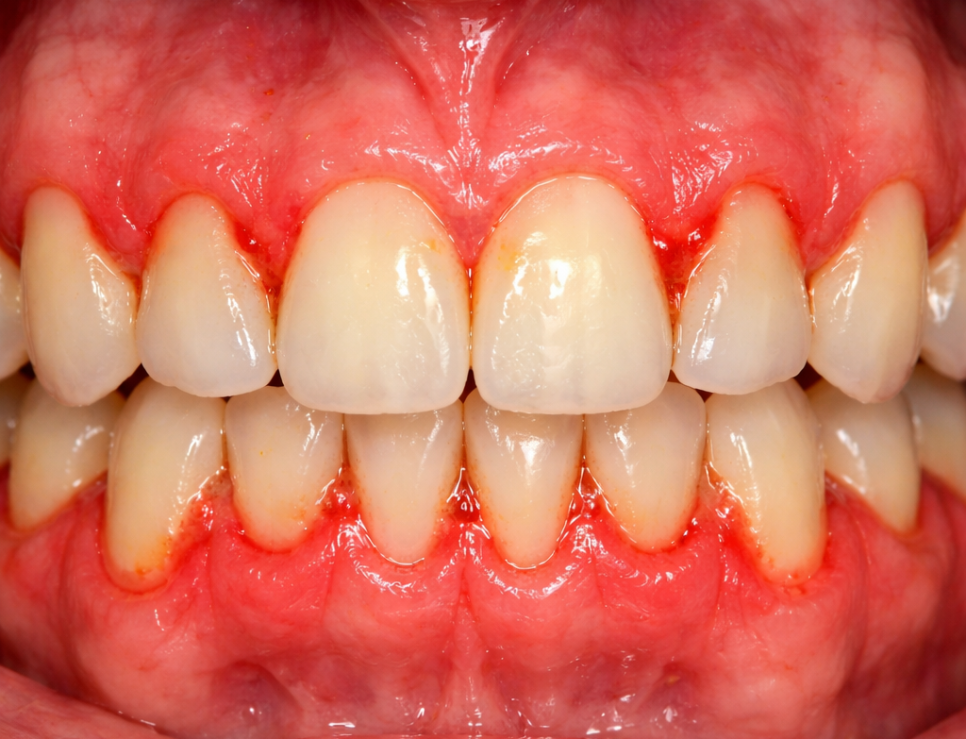

치은염은 잇몸,

즉 치은(gingiva)에만

국한된 염증 상태입니다.

주된 원인은 치아 표면에 형성되는

세균성 막인 치태(dental plaque)로,

제때 제거되지 않으면

잇몸 가장자리를 자극해

붓기와 출혈을 일으킵니다.

이 단계에서는 치아를 지지하는

뼈(치조골)나 인대(치주인대)까지는

손상이 미치지 않은 상태이기 때문에,

전문적인 치태·치석 제거와

올바른 구강위생 관리를 통해

건강한 잇몸 상태로

완전히 되돌릴 수 있다는 것이

치은염의 가장 중요한 특징입니다.

대표적인 증상으로는,

칫솔질 시 출혈,

잇몸의 붉은 변색과

부종이 있습니다.

그러나 통증이 거의 동반되지 않아

스스로 심각성을 인지하기 어렵고,

그 때문에 적절한 관리 시기를

놓치는 경우가 많습니다.